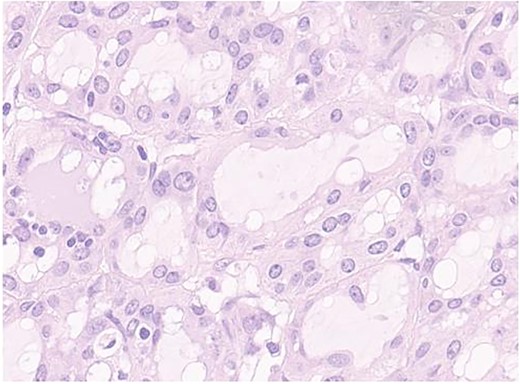

Therefore, surgical excision and histological examination were conducted. The latter reported macroscopically a whitish nodular formation measuring 1.5 × 1 cm and positivity to cytokeratin 7, S100, and mammaglobin, compatible with a MASC, and surgical margins free from invasion (Figs 2–4).

Secretory carcinoma of the salivary gland H&E stained section (40HPF). Tumors aggregate with solid and glandular structure compound of neoplastic cell with eosinophilic vacuolated cytoplasm and monomorfic round vescicular nucley with small nucleoly.